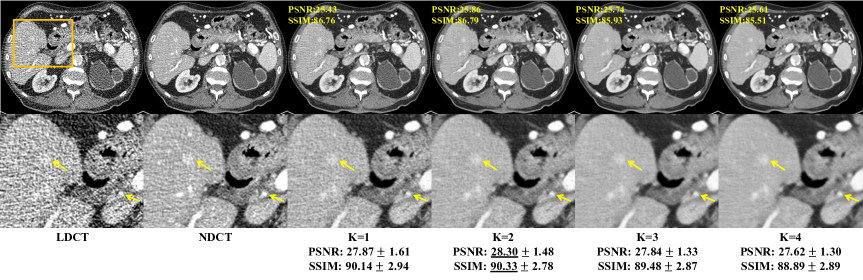

Figure 2: Controllable Noise2Sim results with different denoising levels on the Mayo dataset. The numbers in yellow and black are calculated for the individual case. The numbers in black are respectively the mean and standard deviation values over the test dataset (1136 slices). The second row shows the corresponding ROIs in the yellow bounding boxes. The yellow arrows indicate that structural details are enhanced via image denoising.

Controllability of Noise2Sim with different denoising levels keyed to a single parameter. The similarity parameter k𝑘k defined in the Methods section allows us to control the extent to which image noise is removed. As shown in Fig 2, more noise can be suppressed with a larger parameter k𝑘k. A larger k𝑘k increases the noise independence of similar training samples so that noise can be suppressed more aggressively, as implied by the Noise2Sim theorem. On the other hand, the denoising results may be harmed if k𝑘k is too large, as the zero-mean conditional discrepancy assumed by the Noise2Sim theorem may be compromised. The statistical results in Fig 2 shows that k=2𝑘2k=2 achieves the best trade-off between noise independence and feature similarity. The parameter k𝑘k can be adjusted according to specific down-stream tasks. If image quality can be quantitatively modeled, such as with a neural network and/or a Gram matrix  (?), k𝑘k could be automatically optimized. More practically, several levels of denoising images can be simultaneously presented to radiologists, and thus the best image quality can be determined with the human expertise in loop.